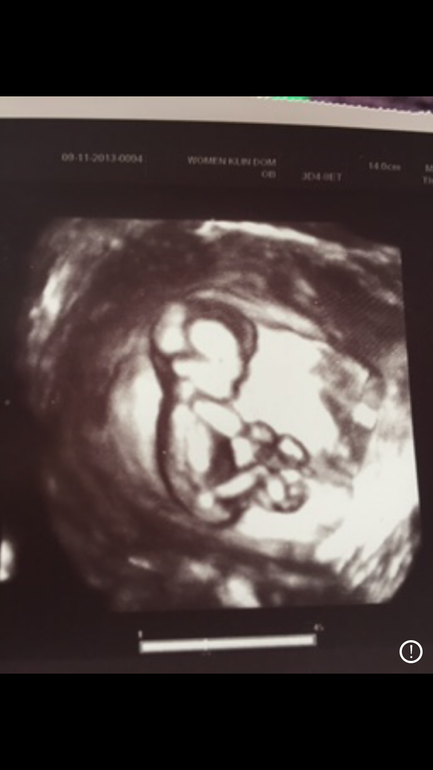

1-ый скрининг)))

Да в 12 недель на 90% сказали мальчик)я не хотела верить)надеялась вдруг девочка)но на след узи подтвердили😊Вот фото 12 недель и сколько то дней было.